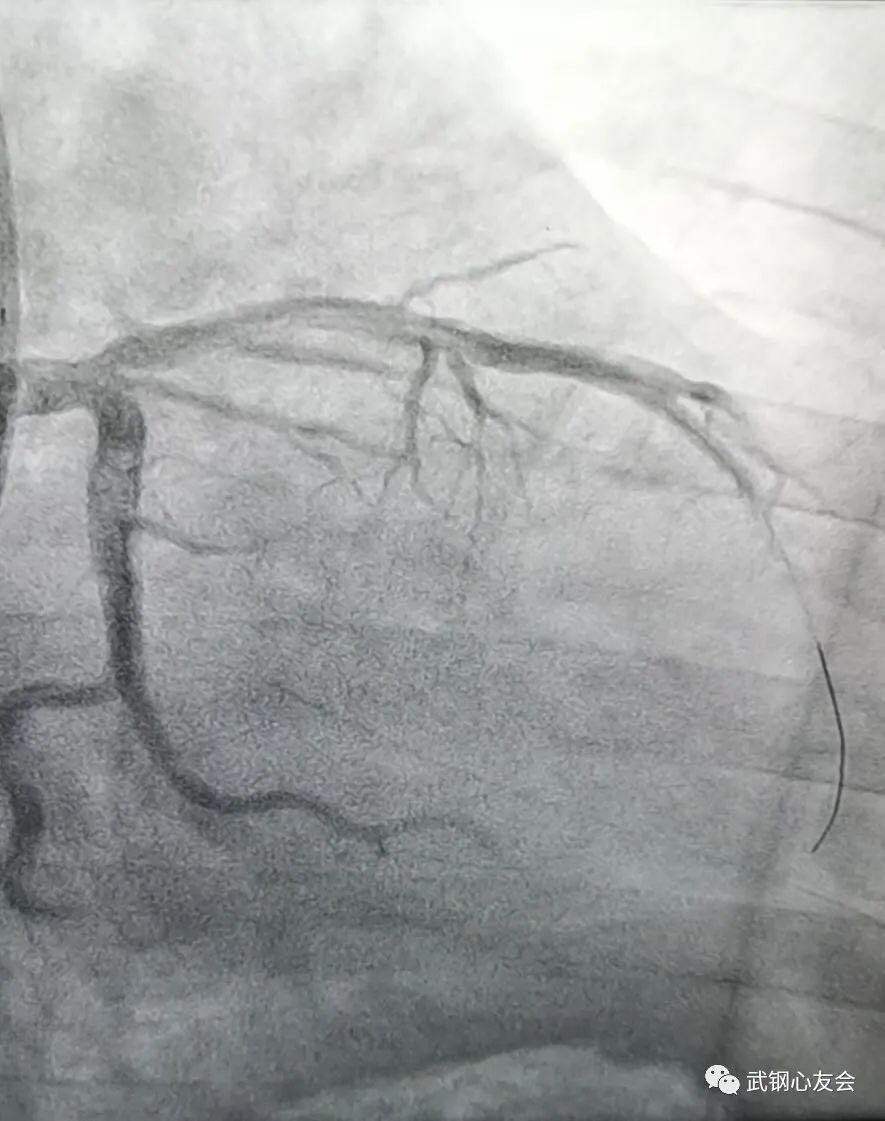

就在安先生出院的同一天,6 月 24 日,43 岁的盛先生(化名)也接受了生物可降解支架植入,术后高度狭窄的冠脉血流恢复良好,盛先生症状得到迅速缓解,观察 2-3 天即可出院,恢复正常工作生活。